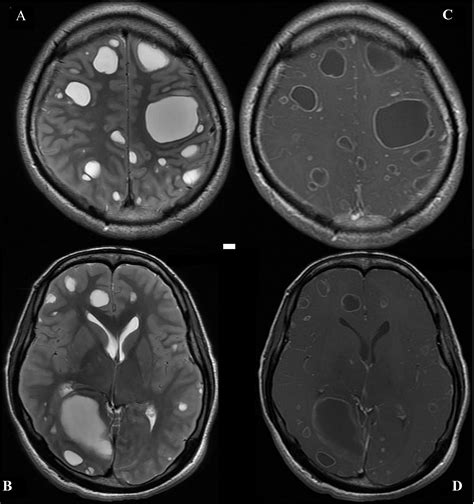

When a radiologist reviews brain imaging, they look for areas that show different signal intensities than the surrounding, healthy brain matter. These differences can be caused by various underlying processes, ranging from inflammation and infection to vascular issues or tumors. Because the causes are so diverse, it is impossible to determine the nature of a lesion based solely on its appearance on a scan; further investigation is almost always required.

• Infections: Abscesses, viral infections (like encephalitis), or fungal infections can create focal areas of inflammation.

• Neoplasms: Both benign (non-cancerous) and malignant (cancerous) tumors can appear as lesions.

Typically, the first step is an MRI with and without contrast. The contrast dye helps radiologists distinguish between different types of tissue and can highlight active inflammation or tumor blood supply. Blood tests may also be ordered to rule out systemic autoimmune diseases, infections, or metabolic issues.

• Follow-up Imaging: A scan performed a few months later to see if the lesion has grown, shrunk, or remained stable.

• Biopsy: In rare cases where a tumor is suspected, a surgical procedure may be required to obtain a tissue sample for laboratory analysis.